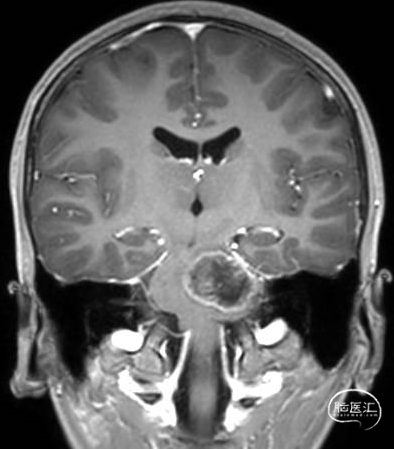

术前MRI

术后MRI